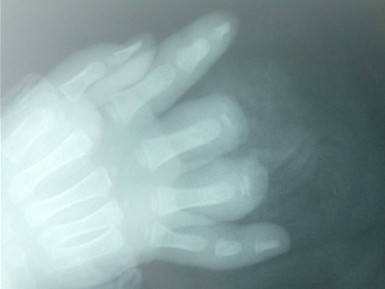

患儿2岁,三角带夹伤致右手中、环指中节基底以远离断。